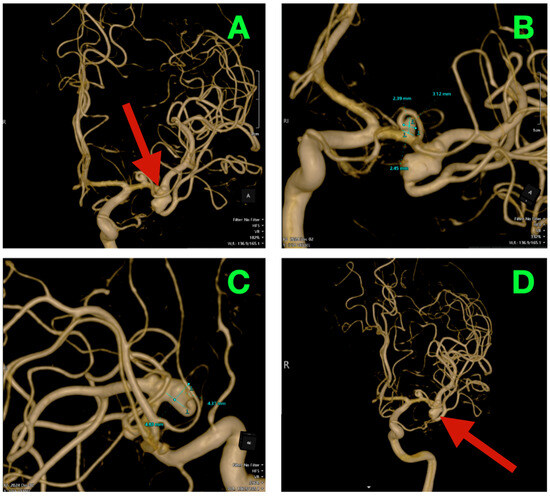

Biplanar DSA of the left internal carotid artery (ICA) was performed under stringent hemodynamic factors to avoid iatrogenic rupture, revealing a tandem aneurysmal arrangement at the proximal MCA (Figure 1A,B). The parameters allowed a frame-by-frame hemodynamic acquisition that indicated peak opacification of the M1 segment at 2.35 s, with complete venous phase clearance at 5.92 s. Both transit times are well within normal values, thus preserving proximal inflow but inducing concern for turbulent microhemodynamics to the aneurysmal neck. The dominant lesion arose exactly at the M1 bifurcation when the parent segment bifurcated into the superior and inferior M2 segments. The aneurysmal neck demonstrated a broad neck diameter of 4.20 mm at its maximal width and bridged the saddle point of the bifurcation, with both M2 origins being partially within the base of the aneurysm. The dome had a maximum height of 4.37 mm, which extended anterosuperiorly and had a slight lateral component toward the opercular−insular boundary. In the sagittal plane, the axis of the dome was at a 43° angle to the M1 axis and 18° in a lateral direction, placing the sac in millimetric proximity to the insular apex and under the lip of the opercular cortex, with only 2.6 mm of distance to the shortest opercular vein—a member of the superficial Sylvian venous complex—the preservation of which was critical to maintain the cortical venous drainage during the surgical dissection of the venous complex. There was subtle lobulation of the contour of the anterosuperior dome, which is a morphological characteristic that occurs with focal wall remodeling under the conditions of chronic high-impulse hemodynamic loading. Proximal to the bifurcation aneurysm and at 3.9 mm from the carotid terminus, a second and much smaller lesion was demonstrated on the dorsal wall of the M1 segment. In stark morphological contrast, this aneurysm was fusiform, which expanded the vessel circumferentially without a neck. The maximum dimensions were 3.12 mm in length, 2.39 mm in width, and 2.45 mm circumferentially. The location was particularly troublesome, as it was buried within the lenticulostriate perforator belt. At least three perforators were clearly demonstrated as arising from the aneurysmal wall and had diameters between 320 and 480 μm, with each perforator draping posteriorly toward the anterior perforated substance. Preoperative assessments, along with the measured flow profiles of the internal carotid artery, indicated that the vessels supplied the superior posterior limb of the internal capsule, the head of the caudate nucleus, and the lateral anterior putamen—all locations where damage could yield limited control of the contralateral hemiplegia and devastating losses in higher-order motor integration.

Figure 1.

Preoperative DSA of the left internal carotid artery. (A) Anteroposterior view demonstrating a broad-necked saccular aneurysm arising from the M1 bifurcation, incorporating the origins of both superior and inferior M2 trunks, with an anterosuperior dome projection toward the opercular–insular interface. Proximal to the bifurcation, a fusiform dilation of the dorsal M1 segment is visible within the lenticulostriate perforator belt. (B) Lateral projection further delineating the dome axis in relation to the insular apex and overlying opercular cortex, as well as the proximity of the fusiform lesion to perforators supplying the posterior limb of the internal capsule and dorsal basal ganglia.

2.3. Three-Dimensional Rotational Angiography (3DRA) and CTA Reconstruction

High-resolution 3D rotational angiographic volumes were collected, and volumetric rendering and CTA were undertaken (Figure 2A–D). This reconstruction optimally adapted to isolate the traditional overlap of vessels or planar angiography and enabled surgical simulation. Additionally, it offered analysis of neck geometry, dome orientation, and angles of take-off of the branches in orthogonal planes, along with great detail to preoperative planning, discarding a virtual “clip trajectory” workable area. The anterosuperior projection of the bifurcation aneurysm was again confirmed, with the dome axis pointing toward the mid-insular cortex. The superior M2 trunk had a narrow angle of take-off at 54° from the superior neck border, while the inferior trunk originated in a more posterior and inferior orientation with a 68° angle that created an acute “tight fork”. This neck geometry significantly reduced tolerance for misalignment of the clip blade because even slight decreases in alignment can add a partial increase in compromise of the lumen—especially if the clip was aligned in a position that would yield a submillimeter misalignment. The neck contained 1.8 mm of orifice from the superior M2 and 1.4 mm of orifice from the inferior M2, as calculated on centerline flow reconstruction. The perforator anatomy of the M1 fusiform aneurysm was elaborated upon with remarkable fidelity. The lenticulostriate had explicitly dissipated perpendicularly on the dorsal wall with their immediate posterior vector direction of the perforated substance. The two biggest perforators measured 460 μm and 420 μm at their origins and were tapering quickly within 1.2 mm of take-off. This made both arteries very sensitive to even glass-like movement in the parent vessel from the clip applied to the bifurcation lesion. The inter-aneurysmal distance was short at 4.7 mm, which allowed for potential mechanical manipulation of the other vessel even if we only performed the dissection on one lesion.

Figure 2.

Three-dimensional rotational angiography and CTA volumetric reconstruction of the left MCA complex. (A) 3DRA, left internal carotid artery injection, anterolateral oblique projection. The bifurcation aneurysm arises at the M1 division point, with the broad neck partially incorporating both superior and inferior M2 origins. Note the anterosuperior dome projection toward the mid-insular cortex and the tight angular divergence of the M2 trunks (“tight fork” configuration), leaving minimal tolerance for clip blade malrotation. (B) 3DRA, orthogonal craniocaudal projection. The dome’s spatial relationship to the superficial Sylvian venous complex is evident, with the shortest opercular vein lying within 3 mm of the aneurysmal wall. The fusiform M1 dilation is visible proximally on the dorsal surface, directly within the lenticulostriate perforator belt. (C) CTA bone–vascular fusion, lateral projection. Depth mapping from the sphenoid ridge shows the bifurcation aneurysm positioned approximately 17 mm deep, corresponding to the mid-third Sylvian fissure corridor, while the fusiform aneurysm lies deeper (~23 mm), just proximal to the genu of the MCA. (D) CTA bone–vascular fusion, inferolateral projection. The lenticulostriate perforators arising from the fusiform M1 segment are visualized with submillimetric resolution, demonstrating perpendicular dorsal take-off toward the anterior perforated substance, underscoring the extreme vulnerability of these vessels to even minimal parent vessel displacement during bifurcation clip application.

Bone surface reconstruction suggested that the bifurcation aneurysm was situated approximately 17 mm deep to the sphenoid ridge, corresponding to the origin of the Sylvian fissure at or near the mid-third Sylvian fissure exposure, while the fusiform aneurysm was much deeper at 23 mm from this same cortical surface landmark, and just proximal to the genu of the MCA.